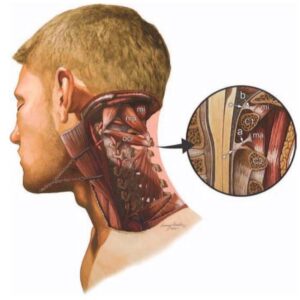

Nervo vago e arteria vertebrale

Il sistema occipito-atlanto-assiale coinvolge direttamente il nervo vago all’uscita del foro lacero posteriore ed è attraversato dall’arteria vertebrale prima che questa entri nel cranio tramite il forame magno. Uno squilibrio del sistema può recare quindi cervicalgie, vertigini, capogiri, sintomi gastro-intestinali, e altri sintomi neurovegetativi legati all’attività neurologica del nervo vago e dall’afflusso dell’arteria vertebrale

Ganglio cervicale superiore

Anteriormente alle masse trasverse di C2 sono presenti i gangli cervicali superiori. Questi gangli fanno parte della catena del sistema ortosimpatico e presentano anastomosi con il nervo vago, il glossofaringeo e l’ipoglosso. Oltre a questi collegamenti, dal ganglio diparte il nervo carotico interno che segue la carotide interna (funzione vaso motrice) e forma il plesso carotideo. Da questo plesso origina una radice del ganglio ciliare che si dirige verso il bulbo oculare. Sempre da questo ganglio origina il nervo carotico esterno, i rami faringei per il plesso faringeo e il nervo cardiaco superiore che partecipa alla formazione del plesso cardiaco. Inoltre sono stati scoperti anche nervi che si dirigono alle strutture dell’encefalo, influenzando funzioni intellettive come l’apprendimento, le onde cerebrali e la secrezione di ormoni come la melatonina. Per tutti questi collegamenti, una disfunzione della seconda vertebra cervicale quindi può influenzare la funzionalità di questi gangli generando vari tipi di sintomi tra ipertensione arteriosa, dolore all’occhio, difficoltà ad addormentarsi, rallentamento dell’apprendimento.